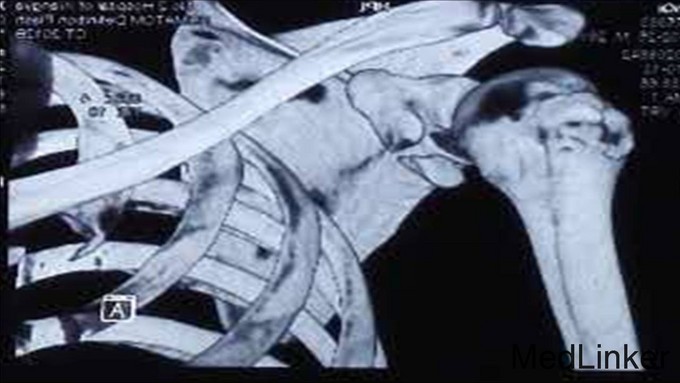

患者谢某某,男性,28岁,已婚 患者坠马后摔伤右肩部,局部肿痛伴活动受限7日 外院就诊摄片示:右肩胛骨折;右肱骨大结节骨折 右上肢外展支架外固定

右肩甲盂骨折